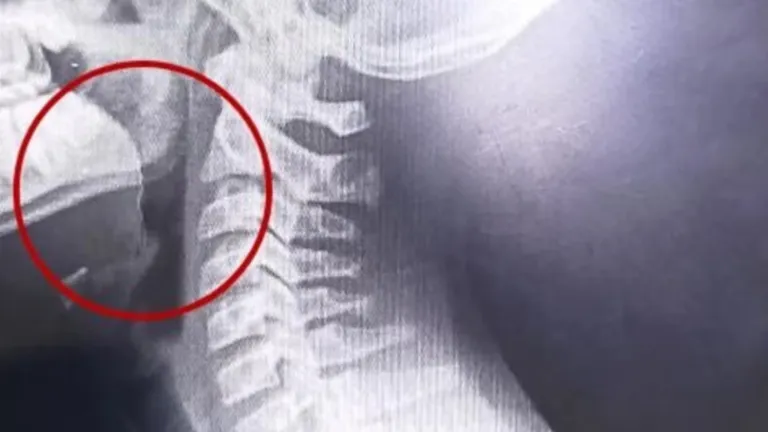

Encontraron que tenía un alambre fino incrustado en la garganta.

En el establecimiento decidieron internarlo de inmediato, y tras una serie de estudios, las placas lograron detectar un elemento inusual en el tracto respiratorio superior. Con ese resultado, le realizaron una laringoscopía y descubrieron que se trataba de un alambre fino que se había incrustado en la garganta del adolescente.